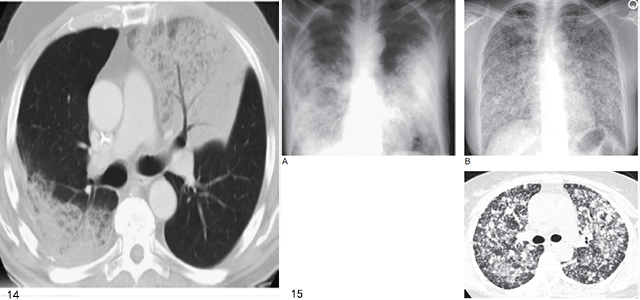

图14 弥漫性细支气管肺泡癌侵犯两上叶,伴实变和空气支气管征

图15 弥漫性细支气管肺泡癌(BAC)

A. 伴双肺实变的BAC;B. 伴两肺模糊小结节;C. 同一患者高分辨率CT 显示弥漫分布的小结节